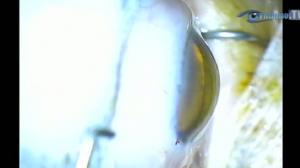

Le patient impossible

Par : Dr Patrice Vo Tan (Paris - France)

Chaîne : Cataracte